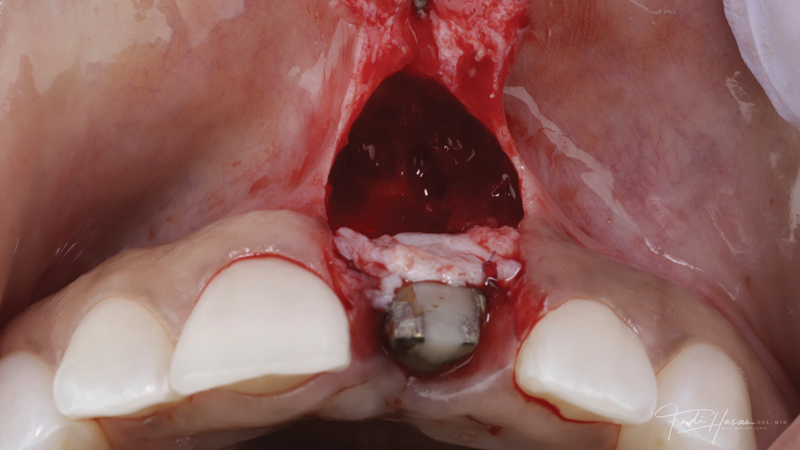

A patient presented for the restoration of an implant that had been placed at the site of tooth No. 9, which exhibited a residual soft-tissue deficiency and an undulating facial soft-tissue morphology (Figure 11). The objective of the treatment was to change the appearance and thickness of the facial soft tissue prior to crown placement to optimize the esthetics and prevent future soft-tissue dehiscence. After flap reflection (Figure 12), a graft was acquired from the patient's tuberosity to augment the supracrestal soft tissue (Figure 13). A volume-stable collagen matrix was then placed to further increase the thickness of the soft tissue adjacent to the implant body (Figure 14), and the flap was sutured closed (Figure 15). Following a 3-month healing period, a positive change in the soft tissue's morphology was apparent; however, its volume remained deficient when compared with that of tooth No. 8 (Figure 16). When the screw-retained crown was delivered, a second graft was acquired from the tuberosity and placed to further increase the volume of the supracrestal soft tissue (Figure 17 and Figure 18). A postoperative healing period of 4 months resulted in an ideal position of the margin of tooth No. 9 with regard to its contralateral counterpart as well as more natural looking soft-tissue morphology and excellent supracrestal soft-tissue thickness (Figure 19 and Figure 20). Eight months postoperatively, the position of the gingival margin and the thickness of the soft tissue had been maintained (Figure 21 and Figure 22).

(13.) A soft-tissue graft from the tuberosity was placed to augment the supracrestal soft-tissue.

Figure 13

(14.) A volume-stable collagen matrix was placed to further increase the thickness of the soft tissue adjacent to the implant body.

Figure 14